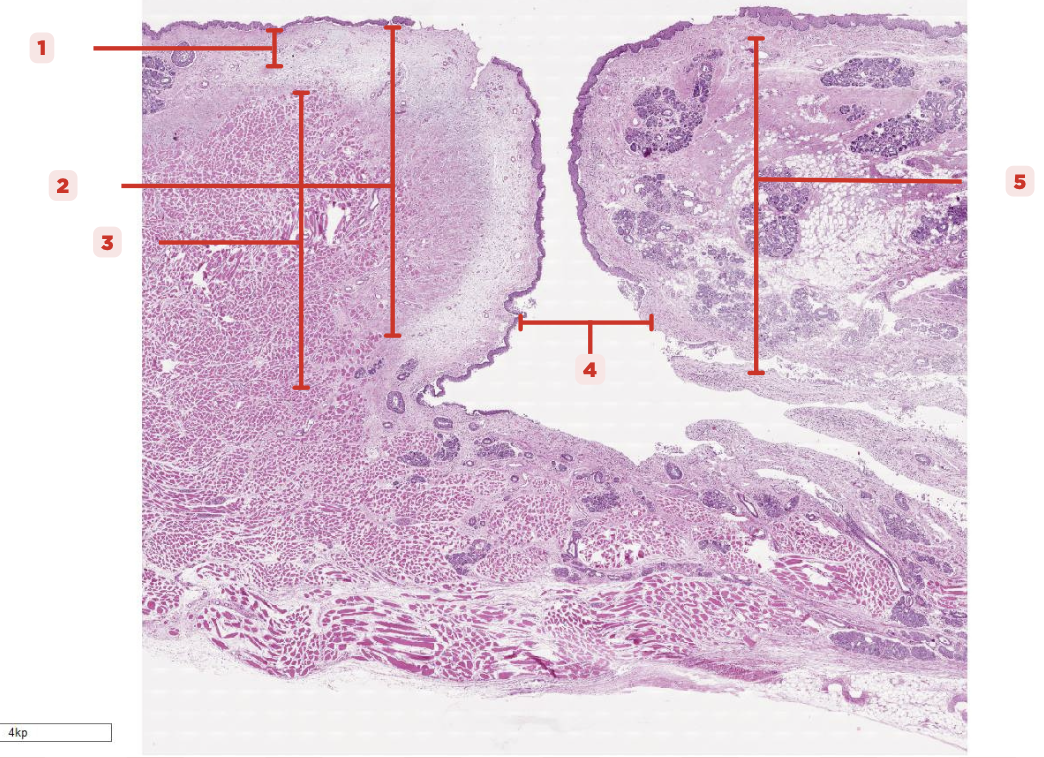

Identify the structure labeled as 1.

Laryngeal Ventricle

Space that separates the true and false vocal cords (#4)

True Vocal Cord

The #2 consists of a lamina propria that includes the vocalis ligament and a group of skeletal muscles known as the vocalis muscle.

Vocalis Ligament

Identify the structure labeled as 1.

True Vocal Cord

Identify the structure labeled as 2.

Vocalis Muscle

Identify the structure labeled as 3.

Laryngeal Ventricle

Identify the structure labeled as 4.

False Vocal Cord

Identify the structure labeled as 5.